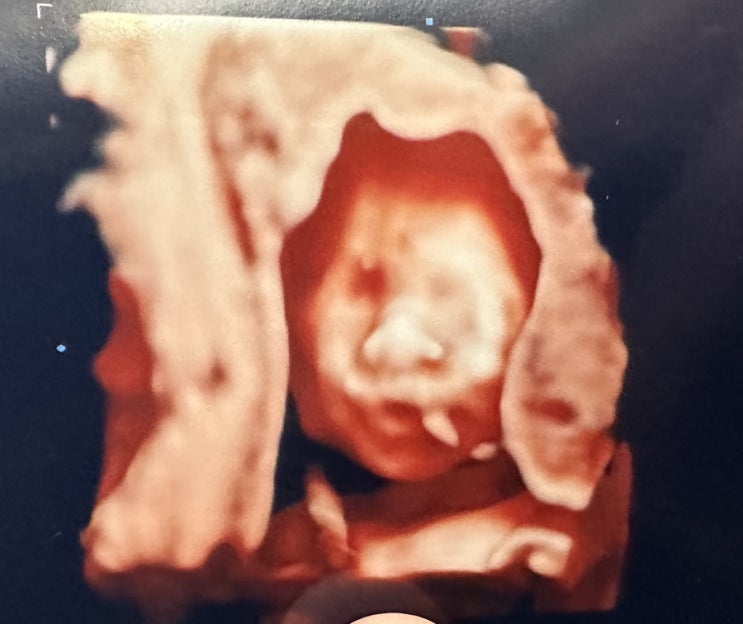

34주~35주 2.2kg 행복이, 얼마 남지 않은 임산부 일상, 성심당 순수롤

32주~33주 아산병원 진료 다녀온지 2주 후, 동네 병원에서 행복이 정기 검진 및 태동 검사를 하고 왔다. 행...